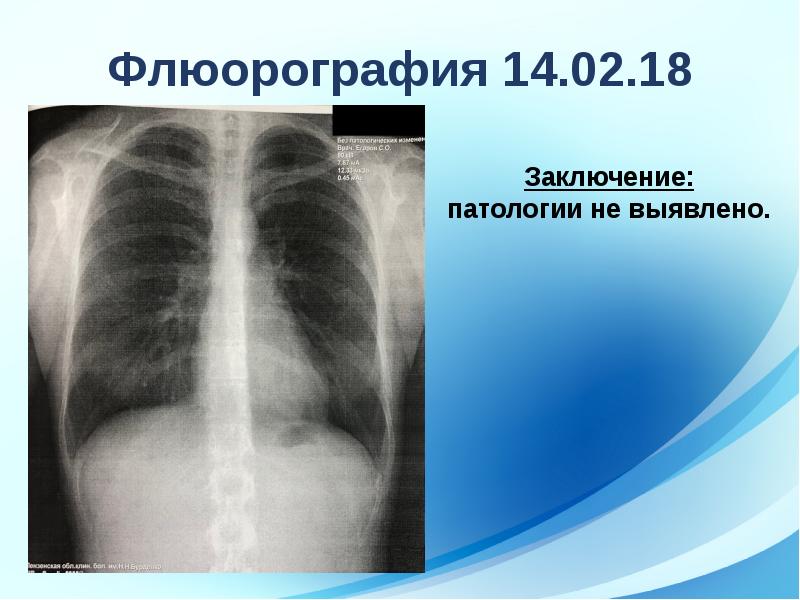

Фотографии рентгеновских снимков без необходимости направления от врача